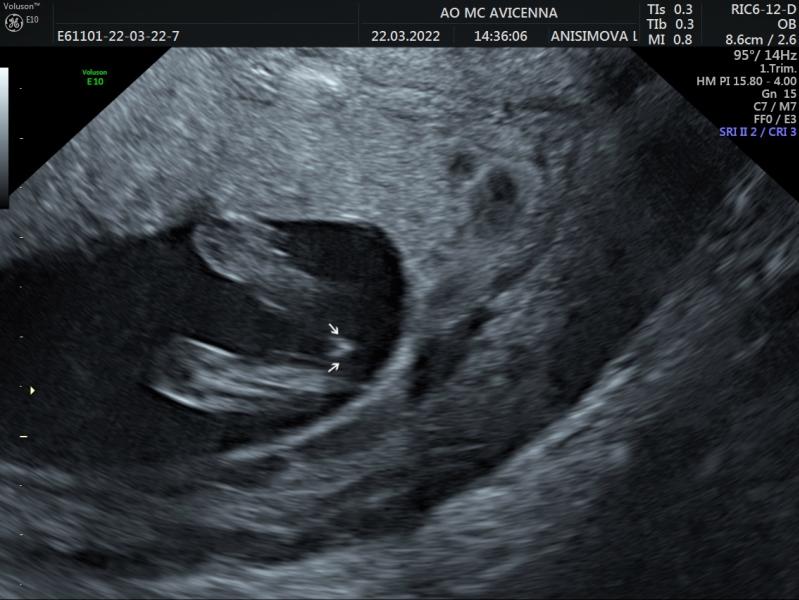

Привет.на 1скрининге сказали сын будет..ходила разговаривала с мальчиком(((вчера на втором сказали дочка🫣.если честно ,думаю что рожу сына)))))проверим насколько моё желание осуществимо...У кого был такой снимок?кого ждали?у меня прям сомнения

Из того, что на снимке, никакой пенис и яйки не вырастут уже)

Раньше 15 недель вообще не информативно смотреть пол по узи. Могут только предположить и угадать или нет)